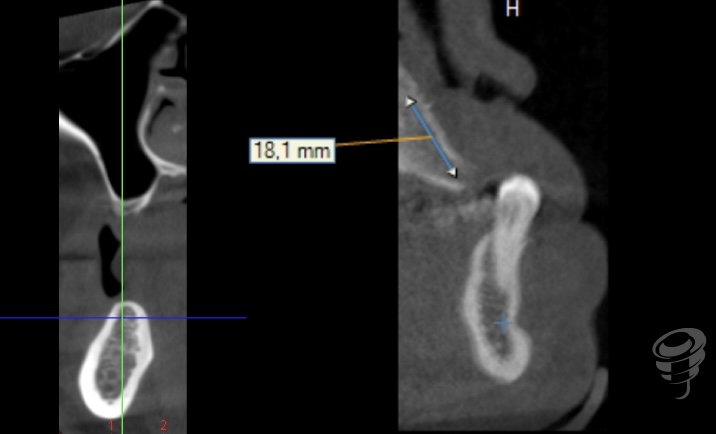

Protocolo Quad Zygoma. (Imagen 26-37)

Por otra parte, el Quad Zygoma nos pemite tratar maxilares con atrofia severa, con posibilidad de carga inmediata, ubicando los implantes en posiciones prostodóncicamente adecuadas que permiten una rehabilitación y mantenimiento convencionales, siendo muy importante para esta técnica evaluar la disponibilidad ósea del cuerpo del cigoma para alojar dos implantes.

Imagen 28 – Valoración Volumen Cigoma